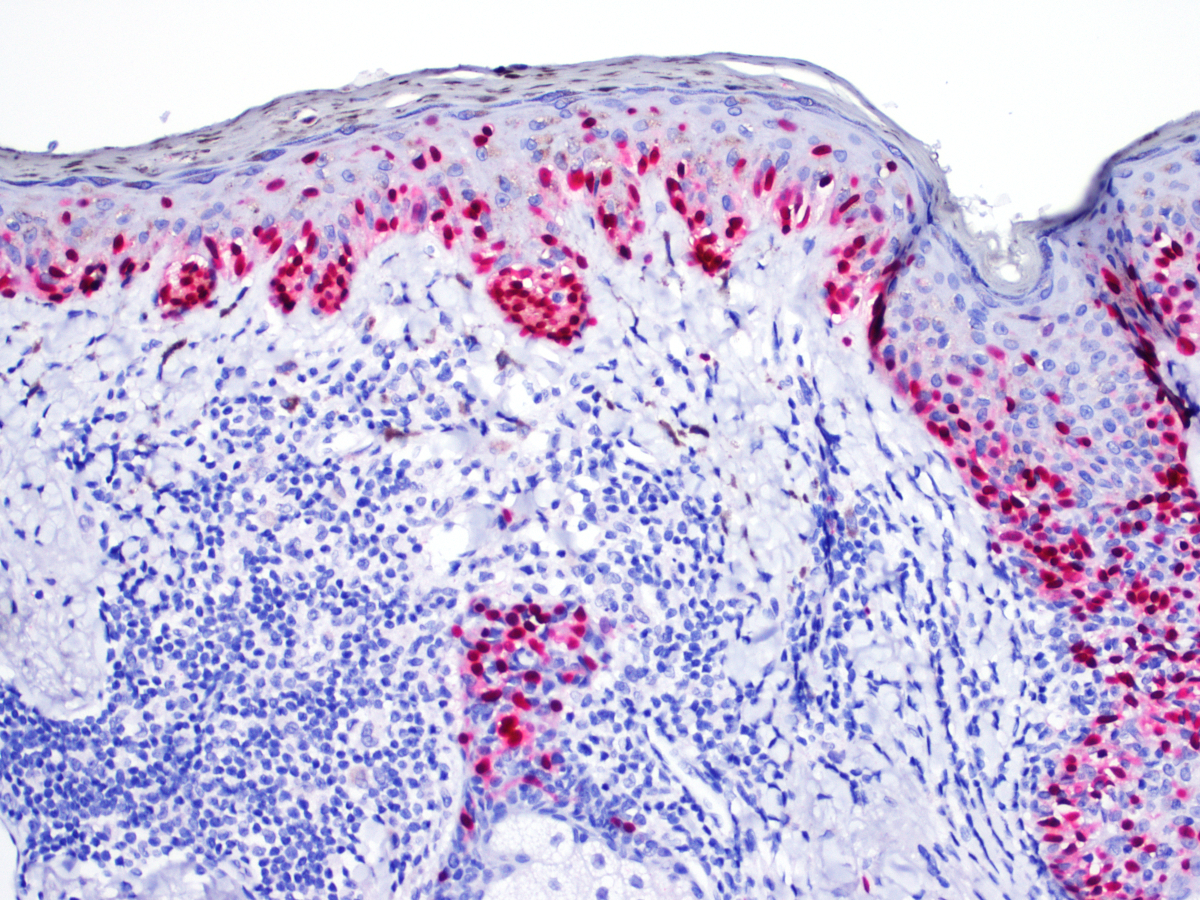

Positive stains

- Immunohistochemistry for MelanA / MART1, SOX10 and MITF may assist in diagnosis by highlighting the arrangement of melanocytes in the epidermis and by assisting in identification of dermally invasive cells (Am J Dermatopathol 2014;36:387, Am J Dermatopathol 2014;36:124)

Microscopic (histologic) images

Contributed by Joseph Gillam, M.D., Jennifer Crimmins, M.D. and Mark Mochel, M.D.